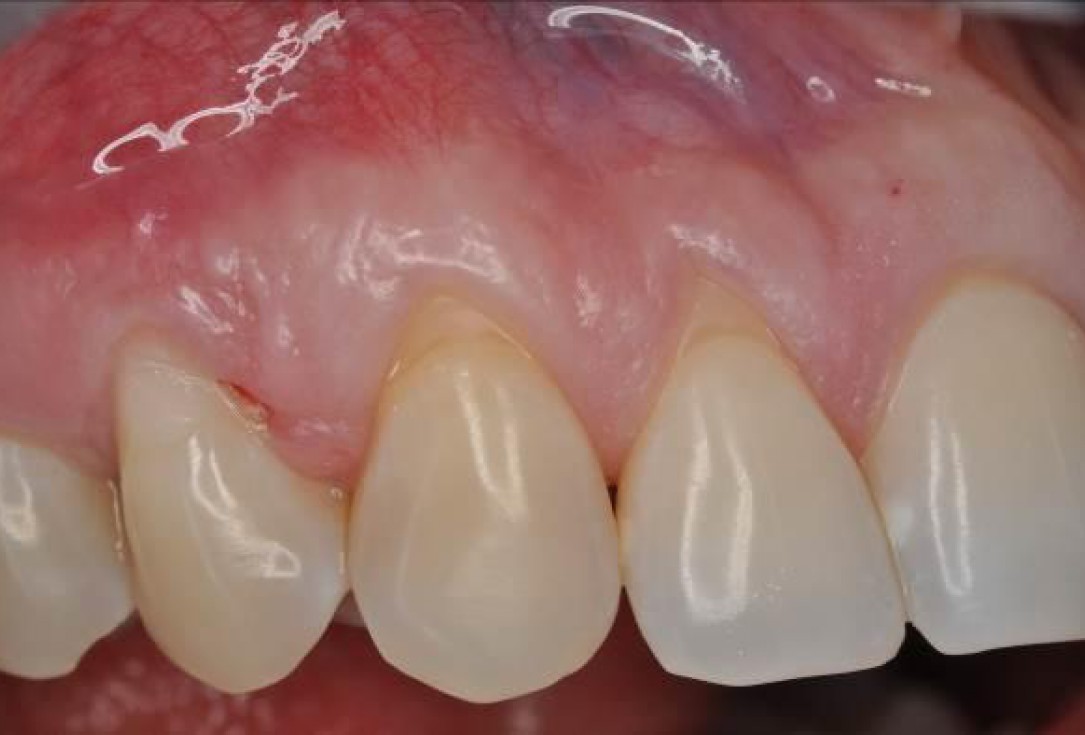

01/06 - Pre-surgical situation. Multiple adjacent gingival recessions at teeth 12, 13 and 14.Multiple gingival recessions treated with the modified coronally advanced flap in conjunction with mucoderm® and Straumann® Emdogain® - Dr. D. B. Hangyási

Pre-surgical situation. Multiple adjacent gingival recessions at teeth 12, 13 and 14.